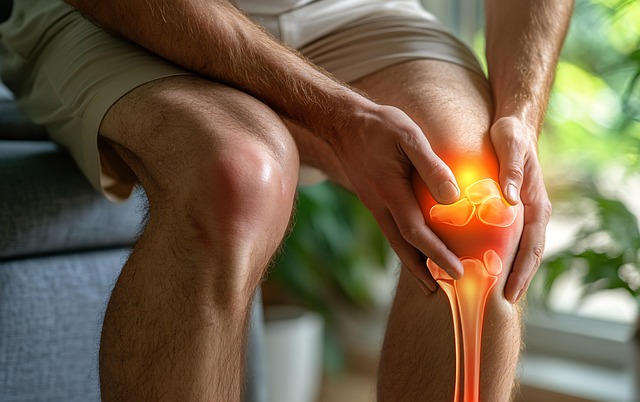

고관절은 걷기, 뛰기, 앉기 등 거의 모든 움직임에 관여하며 체중을 직접 지탱합니다. 연골 손상, 근육 불균형, 점액낭 염증, 과사용 등이 주요 원인입니다. 고관절 내부는 연골·관절막·Labrum·근육·힘줄이 밀집되어 있어, 어디가 문제인지에 따라 고관절 통증 증상이 달라집니다. 사타구니 당김은 내부 구조 문제, 옆쪽 통증은 점액낭 문제, 찝힘은 충돌증후군과 관련 있을 가능성이 높습니다.

2. 대표 고관절 통증 증상 8가지

아래 증상 중 2개 이상 해당한다면 조기 관리가 필요합니다.

- 사타구니 통증

- 엉덩이 깊숙한 통증

- 다리 굽힘·내회전 시 찝히는 느낌

- 걷기 시작할 때 뻐근함

- 양반다리나 오래 앉기가 불편함

- 계단 오르내릴 때 통증

- 움직일 때 딱·드르륵 소리

- 힘 빠짐·불안정감

이런 신호들은 모두 고관절 통증 증상의 대표 패턴이므로 무시하면 악화됩니다.